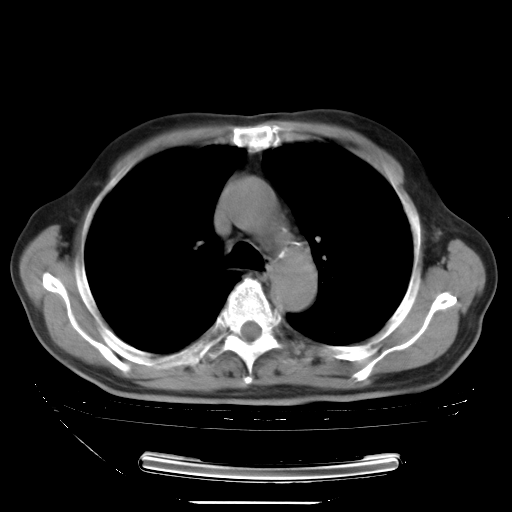

今天复查肺部CT,发现双肺广泛磨玻璃样改变。所以我把3月19日和5月9日相隔50天的肺部CT上传。请大家会诊。

5月9日肺部CT(在4月27日齐鲁医院肺部CT描述部分肺组织磨玻璃样改变,12天后肺组织广泛磨玻璃样改变)

2009年5月9日肺部CT